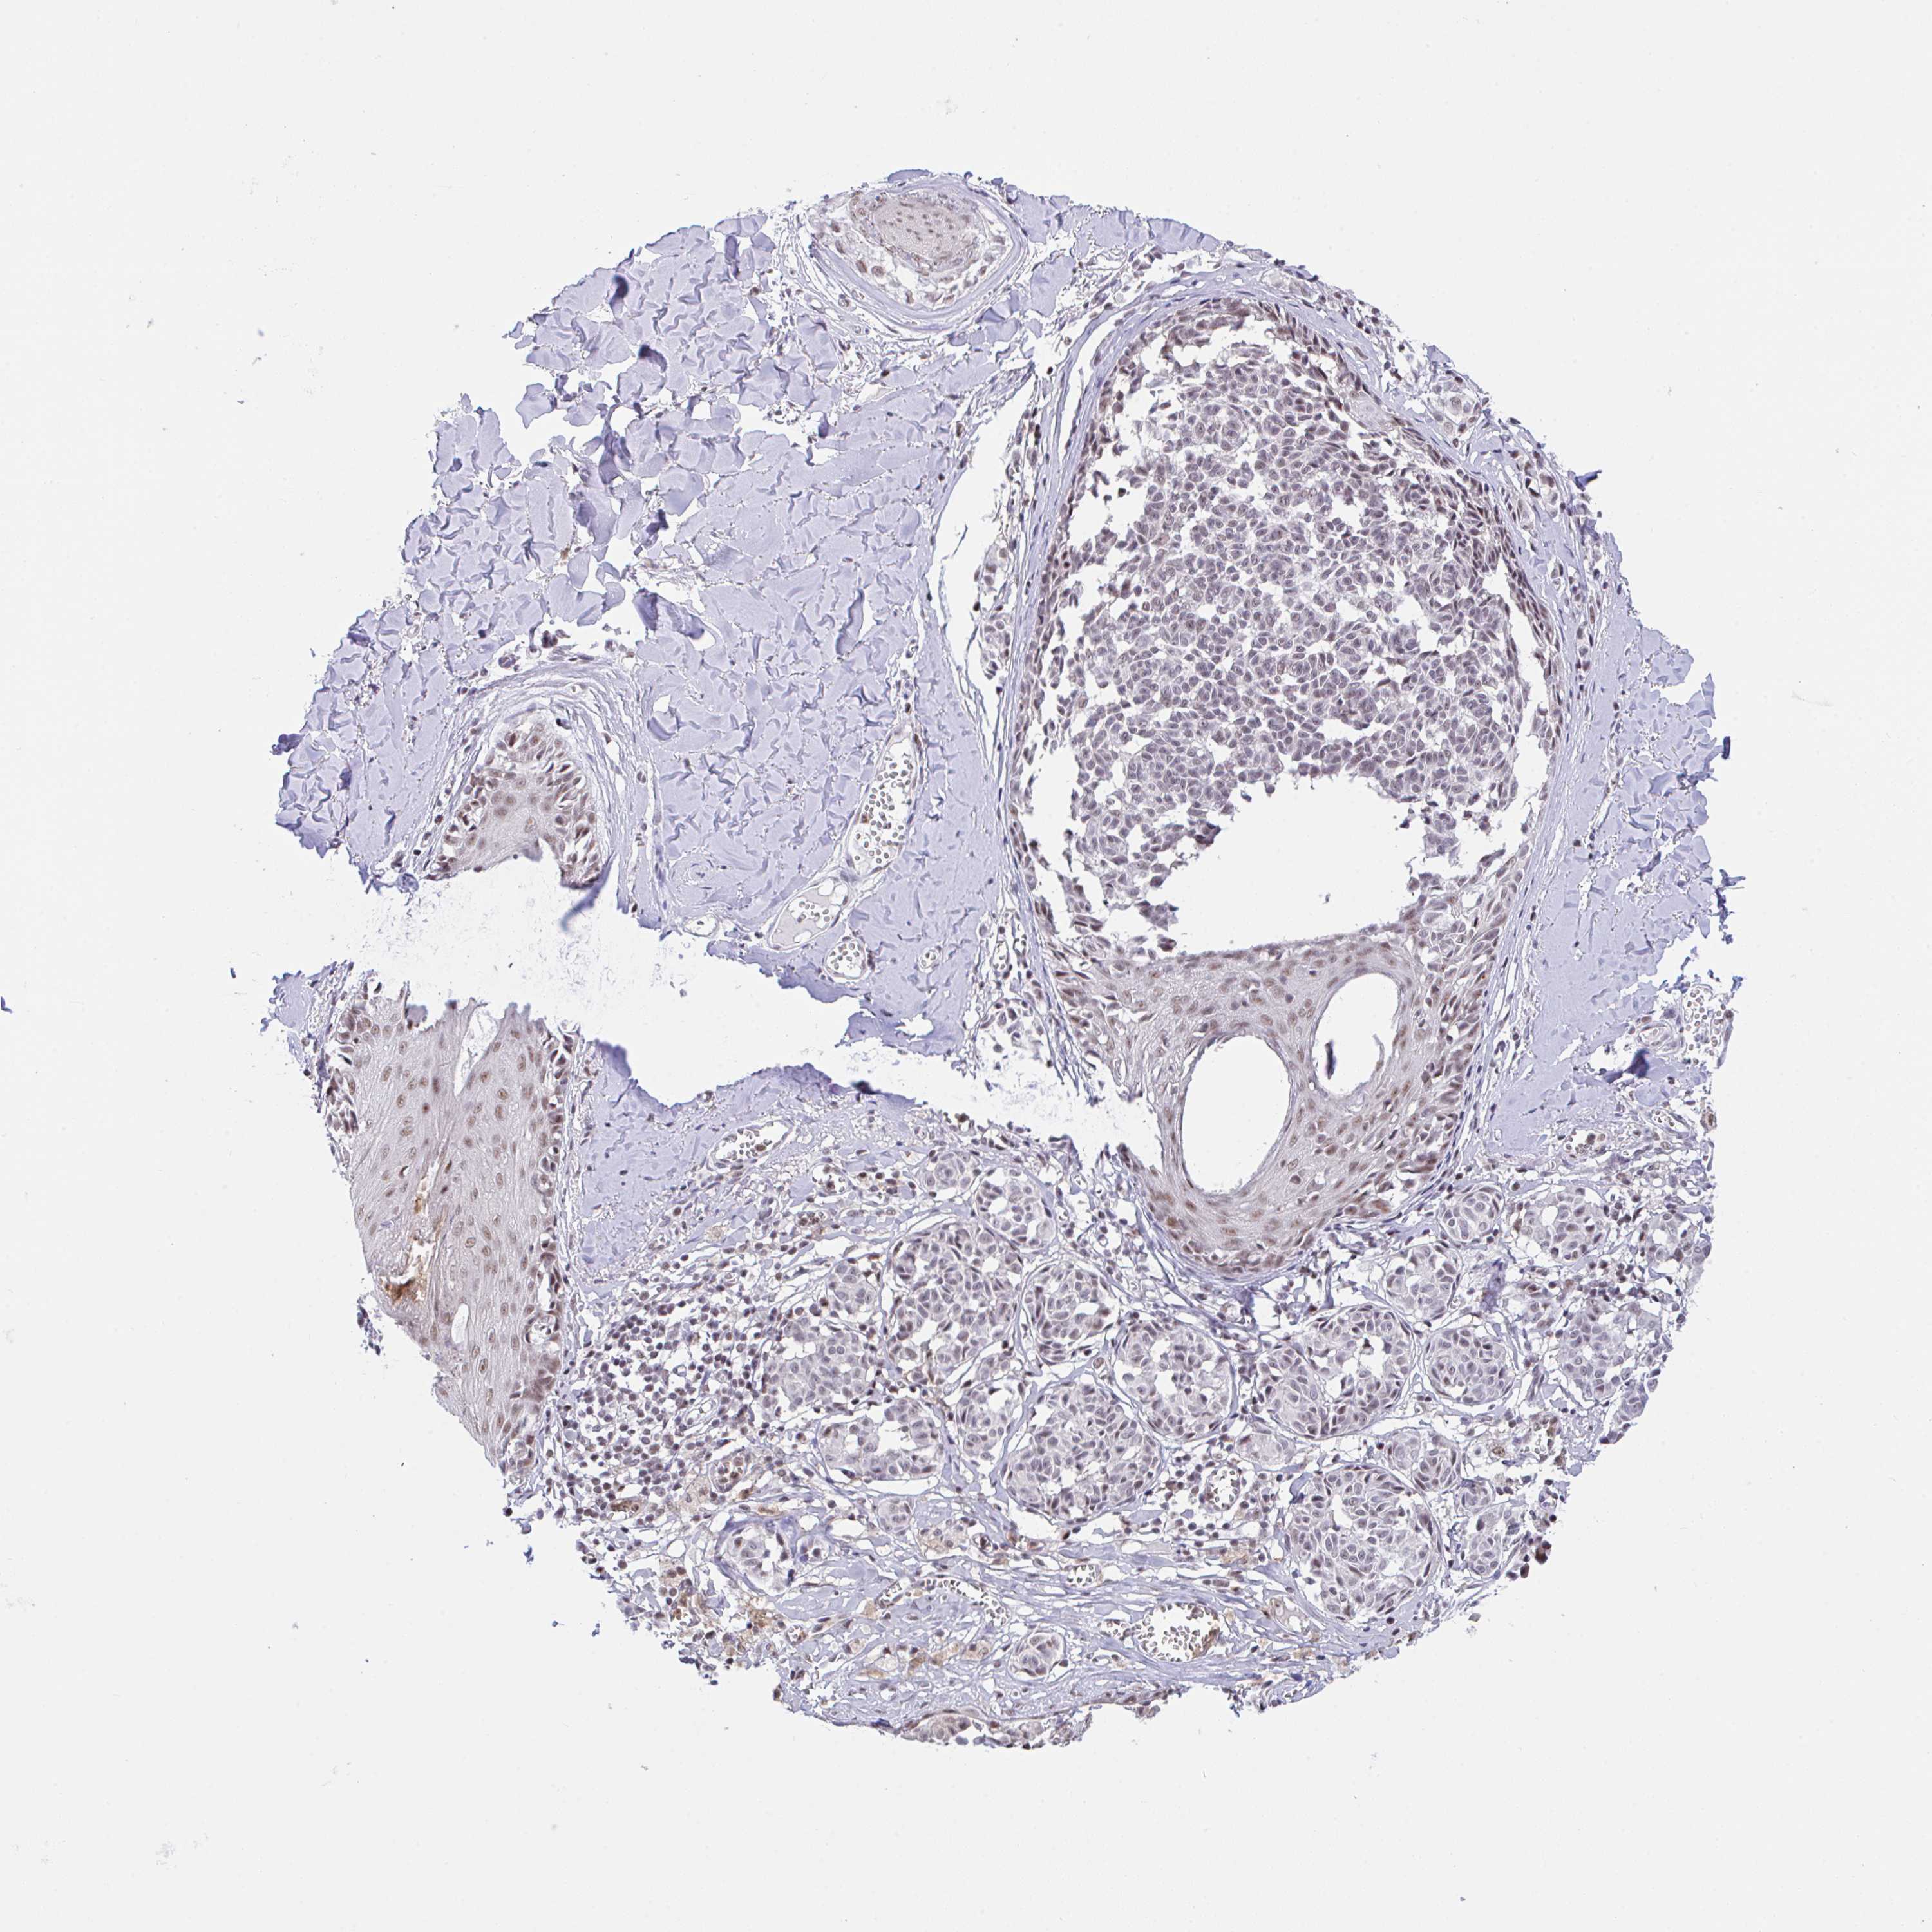

MELANOMA - Protein expressioni

A mouse-over function shows sample information and annotation data. Click on an image to view it in a full screen mode. Samples can be filtered based on level of antibody staining by selecting one or several of the following categories: high, medium, low and not detected. The assay and annotation is described here.

Note that samples used for immunohistochemistry by the Human Protein Atlas do not correspond to samples in the TCGA dataset.

Antibody stainingi

Antibody staining in the annotated cell types in the current human tissue is reported as not detected, low, medium, or high, based on conventional immunohistochemistry profiling in selected tissues. This score is based on the combination of the staining intensity and fraction of stained cells.

Each image is clickable and will lead to virtual microscopy that enables deeper exploration of all samples and also displays staining intensity scores, fraction scores and subcellular localization as well as patient and tissue information for each sample.

Antibody HPA055949

Staining

High

Medium

Low

Not detected

Intensity

Strong

Moderate

Weak

Negative

Quantity

>75%

75%-25%

<25%

None

Location

Nuclear

Cytoplasmic/membranous

Cytoplasmic/membranous,nuclear

Malignant melanoma, NOS

Malignant melanoma, Metastatic site